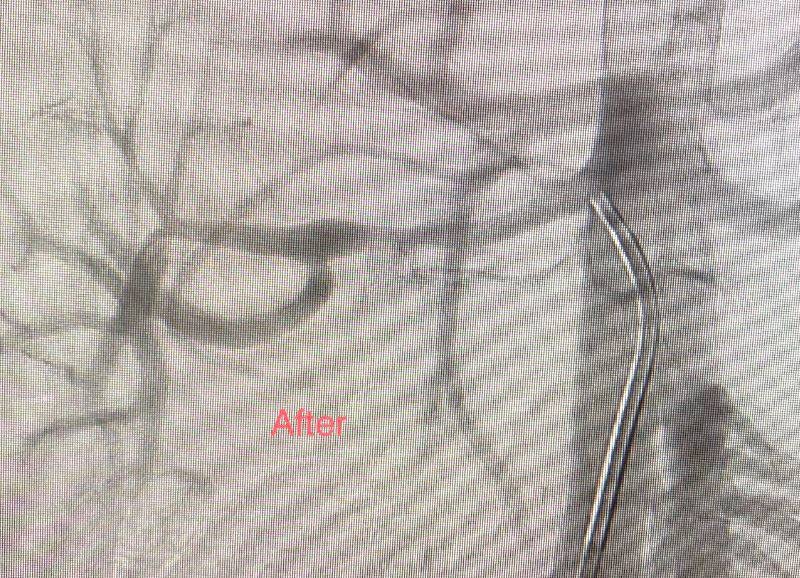

نجح فريق الأشعة التداخلية بمدينة الملك سعود الطبية من إنقاذ طفل (7 سنوات) ارتفع ضغط الدم الشرياني عبر علاجه بالأشعة التداخلية في حالة هي الأولى من نوعها بالمدينة. وكشف رئيس القسم الدكتور عزت باصهي أن خللا في التنسج العضلي الليفي أدى إلى تضييق الشرايين المغذية للكلى وقصور التروية الدموية لأنسجتها، وهي حالة نادرة من مسببات ارتفاع ضغط الدم، فيما تمكن الفريق من التدخل لتوسيع الشريان المغذي للكلية اليمنى عبر القسطرة والبالون الطبي، ما نتج عنه انخفاض مباشر في ضغط الدم، ووقف جميع الأدوية الخافضة للضغط. وغادر الطفل المدينة بعد 48 ساعة من الإجراء على أن تتم متابعته بشكل منتظم.